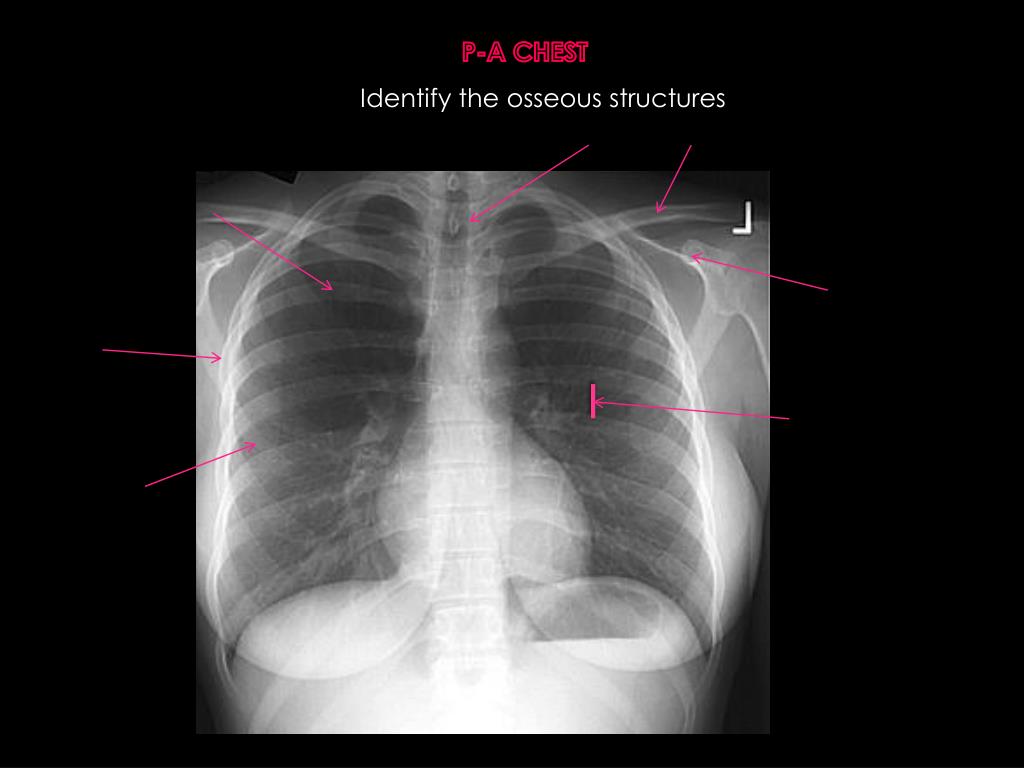

3. P-A CHEST Identify the osseous structures

4. P-A CHEST Identify the osseous structures T-2 v. body clavicle Right 5th posterior rib Coracoid process Right 5th lateral rib 7th left intercostal space Right 5th anterior rib